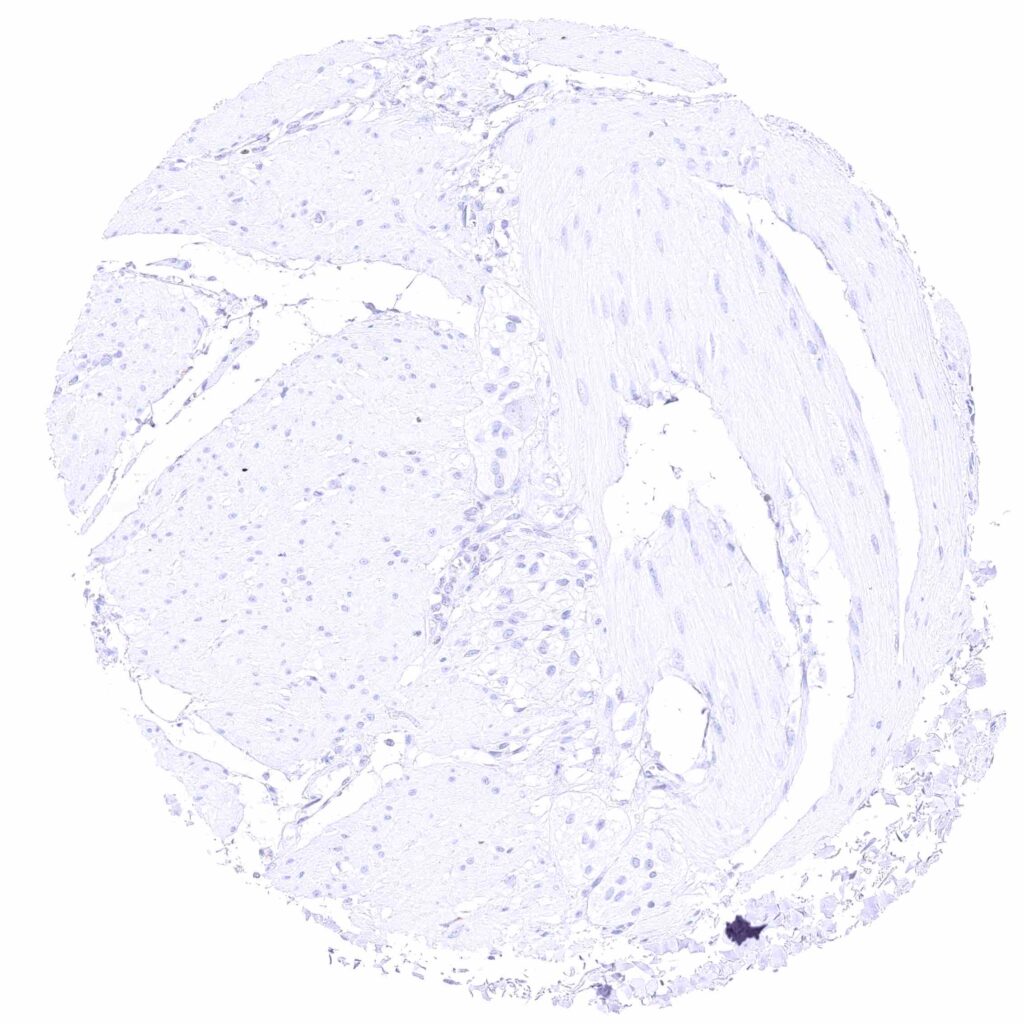

Urinary bladder, muscular wall